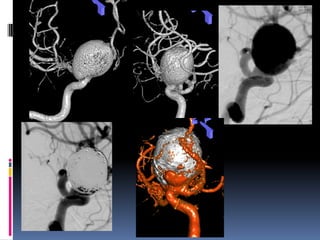

38 yr old male patient, 2-day old SAH

Known hypertensive

Clinically grade II

Small Blister/dissecting Friable, continued growth, re-rupture

Classical blister aneurysm

34-year M, SAH

38 yr oldmale patient, 2-day old SAH Known hypertensive Clinically grade II Small Blister/dissecting Friable, continued growth, re-rupture